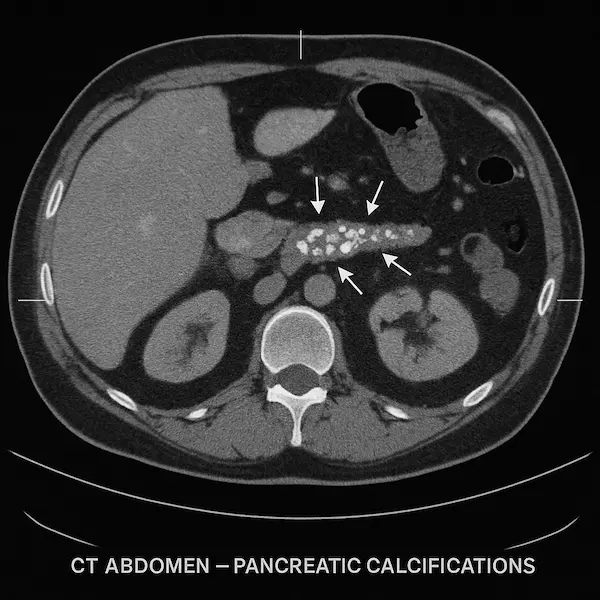

- CT pancreas protocol: the main staging scan

- MRI/MRCP: for bile duct and pancreatic duct detail

- EUS (endoscopic ultrasound) with biopsy: most accurate for tumour confirmation